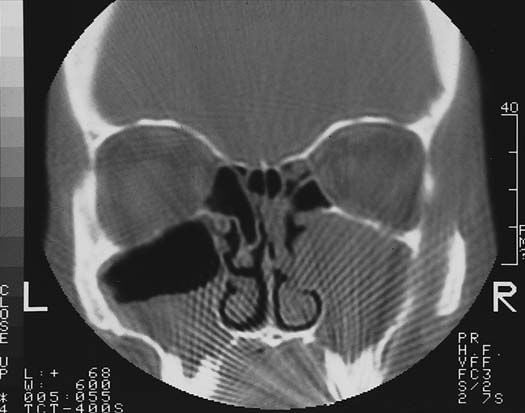

A gyulladásos folyamatok során fehérvérsejtekből, szövettörmelékből, baktériumokból és savóból álló, sűrű, sárgásfehér folyadék. Ha a gennyes gyulladás területén az eredeti szövetállomány felbomlik, a sejtek elpusztulnak, gennyes beolvadás jön létre. A gennyes beolvadás során tokkal körülhatárolódó, gennyel telt üreg képződik: ez a tályog.Az ilyen gennyes, gyulladásos folyamatok az agy állományában is tályogképződést okoznak. A friss agytályog határa nem éles, néhány hónap alatt azonban kötőszövetes tok veszi körül. Ezért a tályog nyomja a környező idegrendszeri képleteket, az agyvelőállományt, az idegsejteket és az idegpályákat.Az agytályog méretétől és elhelyezkedésétől függően különböző idegrendszeri tüneteket okozhat. A specifikus idegrendszeri tünetek mellett általános tünetek, láz, levertség, fejfájás, hányás is felléphetnek.A tályogképződést minden esetben valamilyen gennykeltő baktérium okozta gyulladás előzi meg. A tályog üregét kitöltő genny fehérvérsejtekből, szövettörmelékből, baktériumokból és savóból álló, sűrű, sárgás-fehér folyadék.A közvetlenül az agyat megtámadó bakteriális fertőzés bakteriális agyvelő- és agyhártyagyulladást okoz. A fertőzés az agyállomány környékén kialakult gennyes folyamatokból is átterjedhet az agyra, és a szervezetben máshol kialakult gócokból, a véráram útján is az agyba kerülhet. Az agytályog a nyílt koponyasérülésnek is gyakori szövődménye.Az agytályog igen súlyos, életveszélyes megbetegedés. A gennyes tályog növekedése közben összenyomja, roncsolja az agyállományt. Sok esetben a tályog eltávolítása után maradandó idegrendszeri károsodások maradnak fenn.A kezeletlen agytályog, az általános gyulladásos tünetek és a térszűkítő folyamat halálos kimenetelű lehet. Az időben felfedezett, letokolt agytályog műtéti kilátásai viszont igen jók, a beteg maradéktalanul gyógyul.